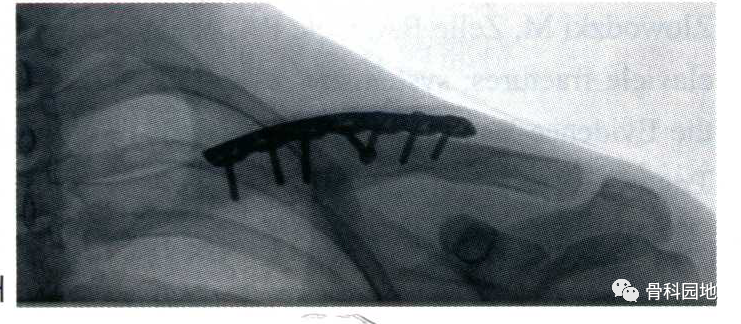

如果无法置入1枚拉力螺钉,建议在两侧各置ru入4枚螺钉。

简单骨折或主骨折线比较稳定的骨折,可在骨折处进行加压固定。 -

如果骨折粉碎或不稳定,接骨板需放置在中立位。 -

注意不要侵入锁骨下间隙和该部位的重要结构。 -

通常建议钻孔时在锁骨下面插入器械进行保护,螺钉均外露1圈螺纹。 -